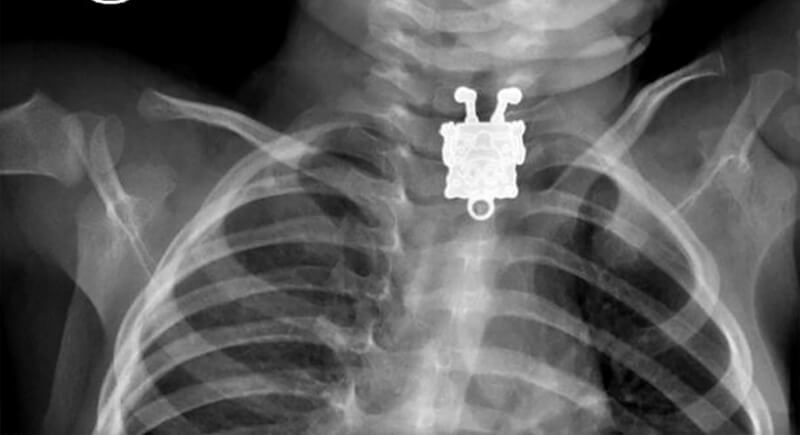

Spongebob Pendant

Credit: 10tv

Doctors reviewing a toddler’s X-ray didn’t expect to see SpongeBob’s face staring back. It turned out to be a small pendant from his sister’s jewelry. Though the pendant rested in his throat, the child showed no distress. Using a camera and small forceps, the medical team safely extracted it.